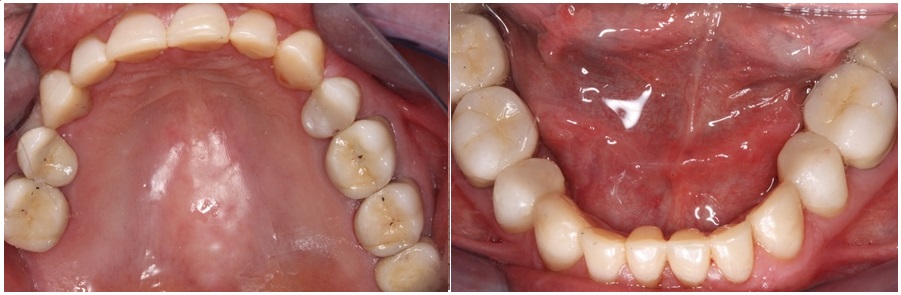

Το βασικό χαρακτηριστικό της αποτριβής είναι οι επίπεδες, λείες και γυαλιστερές επιφάνειες στα δόντια.

Οι επιφάνειες αποτριβής βρίσκονται εκεί όπου τα δόντια έρχονται σε επαφή όταν κλείνουν μεταξύ τους και ξεκινούν πολλές φορές από νεαρή ηλικία όπως στην κυρία της φωτογραφίας η οποία αν και μόλις 25 ετών, εμφανίζει ήδη εικόνα δοντιών που συναντάται σε ασθενείς με πολύ μεγαλύτερη ηλικία.

Βλέπουμε στην ακόλουθη φωτογραφία την χαρακτηριστική εικόνα του χαμόγελου των δοντιών ενός ασθενούς στο ιατρείο μου καθώς και τις λείες, κοφτερές επιφάνειες που έχουν δημιουργηθεί στα πρόσθια δόντια τόσο της άνω όσο και της κάτω γνάθου από την αποτριβή.